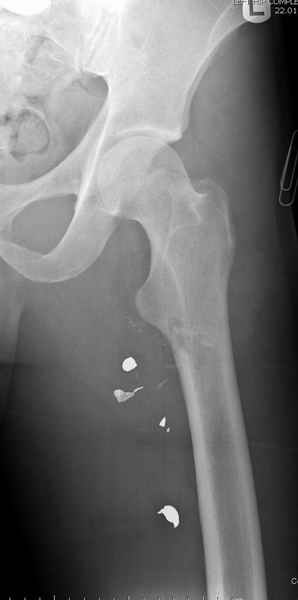

Больной с огнестрельным переломом бедра с вовлечением около 15% медиального кортекса, входное отверстие около 1 см в диаметре; стабильный, без сосудистых и неврологических признаков.

Входные маленькие отверстия от ранении просто игнорируются, никаких дренажей, как любое колотое ранения, они закрываются и были случаи через месяц. Конечно, ведется профилактика открытых ранении: сыворотки и т.д., но еще самое главное уделяем профилактике образования перелома из-за стресса в результате дефекта кортикального слоя.

Литературные данные о влиянии кортикального дефекта на стрессовые переломы в длинных трубчатых костях в основном встречаются в онкологии, например кортикальный дефект более 50% имеет больше шанса стрессовых переломов, чем в нашем случае.

Учитывая, что больной получил травму не во время визита в церковь, и он является одним из представителем 40 миллионного “outstanding itizen”, без медицинской страховки, без работы в свои 39 лет, и без надлежающей ортопедической дисциплины у которого отсутсвует страх стрессового перелома, было рекомендовано оперативное лечение: профилактическое антеградное интрамедуллярное штифтование.

Методика штифтования при отсутствии большой зоны перелома как при онкологических профилактических штифтованиях, расверливание интрамедуллярного канала проводим с предварительным наложением дополнительного дренажного отверстия в дистальном отделе бедра (в данном случаи в канале оставили 6.5 мм канюлированный шуруп), иначе при создании давления в канале во время сверления имеется опасность эмболизации легочной артерии тромбом.